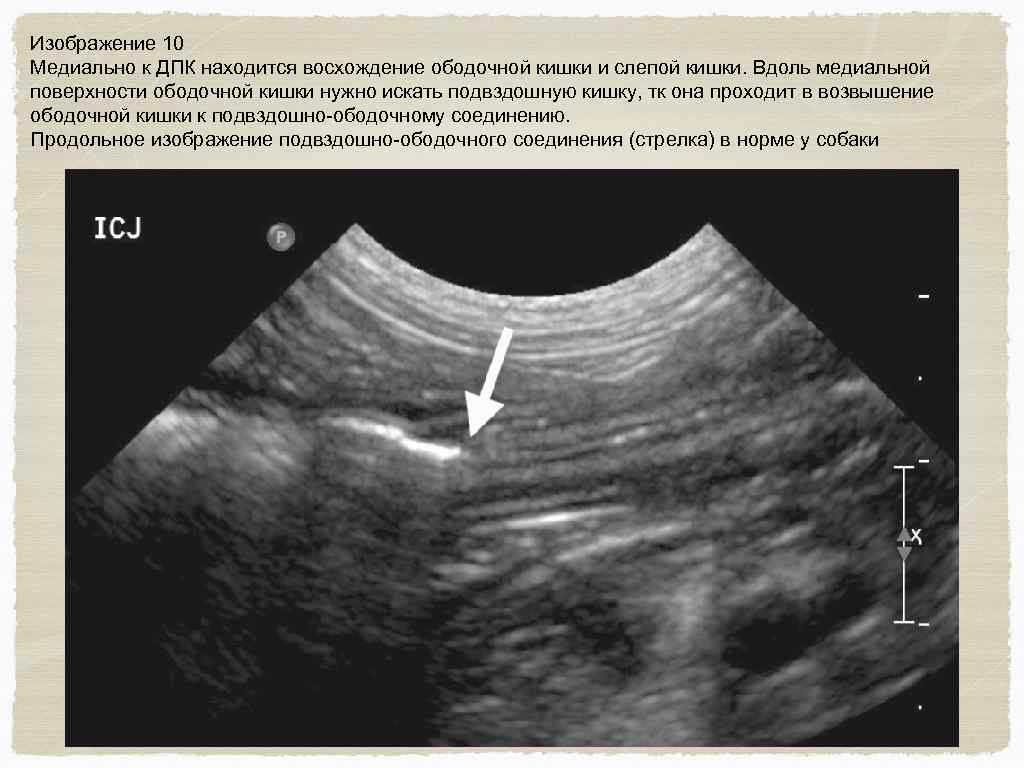

Желудочно-кишечный тракт и поджелудочная железа Исследование проводится в среднем отделе брюшной полости ; установите датчик по длинной оси каудально к печени, так чтобы была видна поперечная проекция желудка. Сдвиньте датчик каудально для определения ободочной кишки в поперечной плоскости (изображение 6) Левая доля поджелудочной железы расположена между желудком и ободочной кишкой, прилегает к селезеночной вене, которая пересекает брюшную полость слева на право и формирует воротную вену. (изображение 7) Вращайте датчик в поперечной плоскости и двигайте его вдоль правой стороны желудка в пилоро-дуоденальное соединение. (изображение 8) Вместе с датчиком, лежащим в поперечной плоскости (с пометкой правой стороны пациента) , следуйте дистально двенадцатиперстной кишки

Изображение 10 Медиально к ДПК находится восхождение ободочной кишки и слепой кишки. Вдоль медиальной поверхности ободочной кишки нужно искать подвздошную кишку, тк она проходит в возвышение ободочной кишки к подвздошно-ободочному соединению. Продольное изображение подвздошно-ободочного соединения (стрелка) в норме у собаки